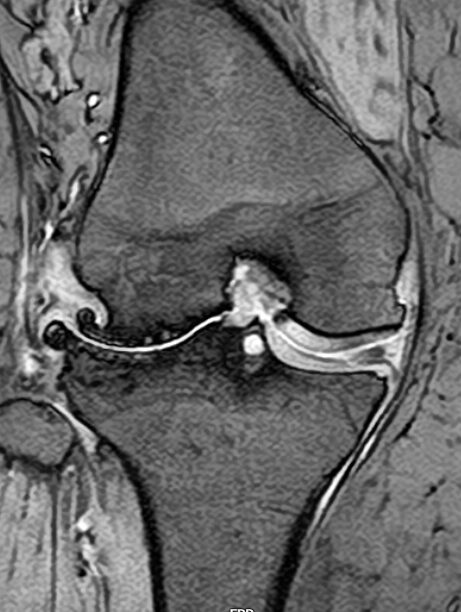

- MRI検査のご予約